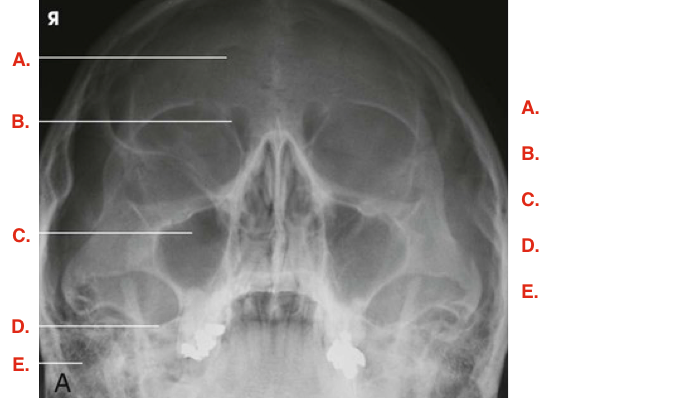

Question

Label the image

Image:

81c44ff7-83a7-4753-bb70-ec9839eab8f7 (image/png)

Answer

maxillary sinus

ethmoidal sinuses

mandible

vomer

sphenoidal sinus

pharynx

petrosa